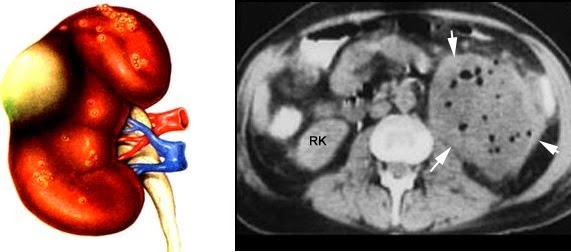

Un absceso renal es la presencia de pus dentro del riñón, y debe tratarse de manera inmediata y agresiva, pues de no hacerlo, es mortal. En la tomografía las flechas indican la colección de pus en el parénquima renal.

Si bien la ecografía y urografía excretoras son de ayuda, el examen de elección es la Tomografía.

En ella se puede delimitar el absceso renal, y conocer si este ha salido del riñón.